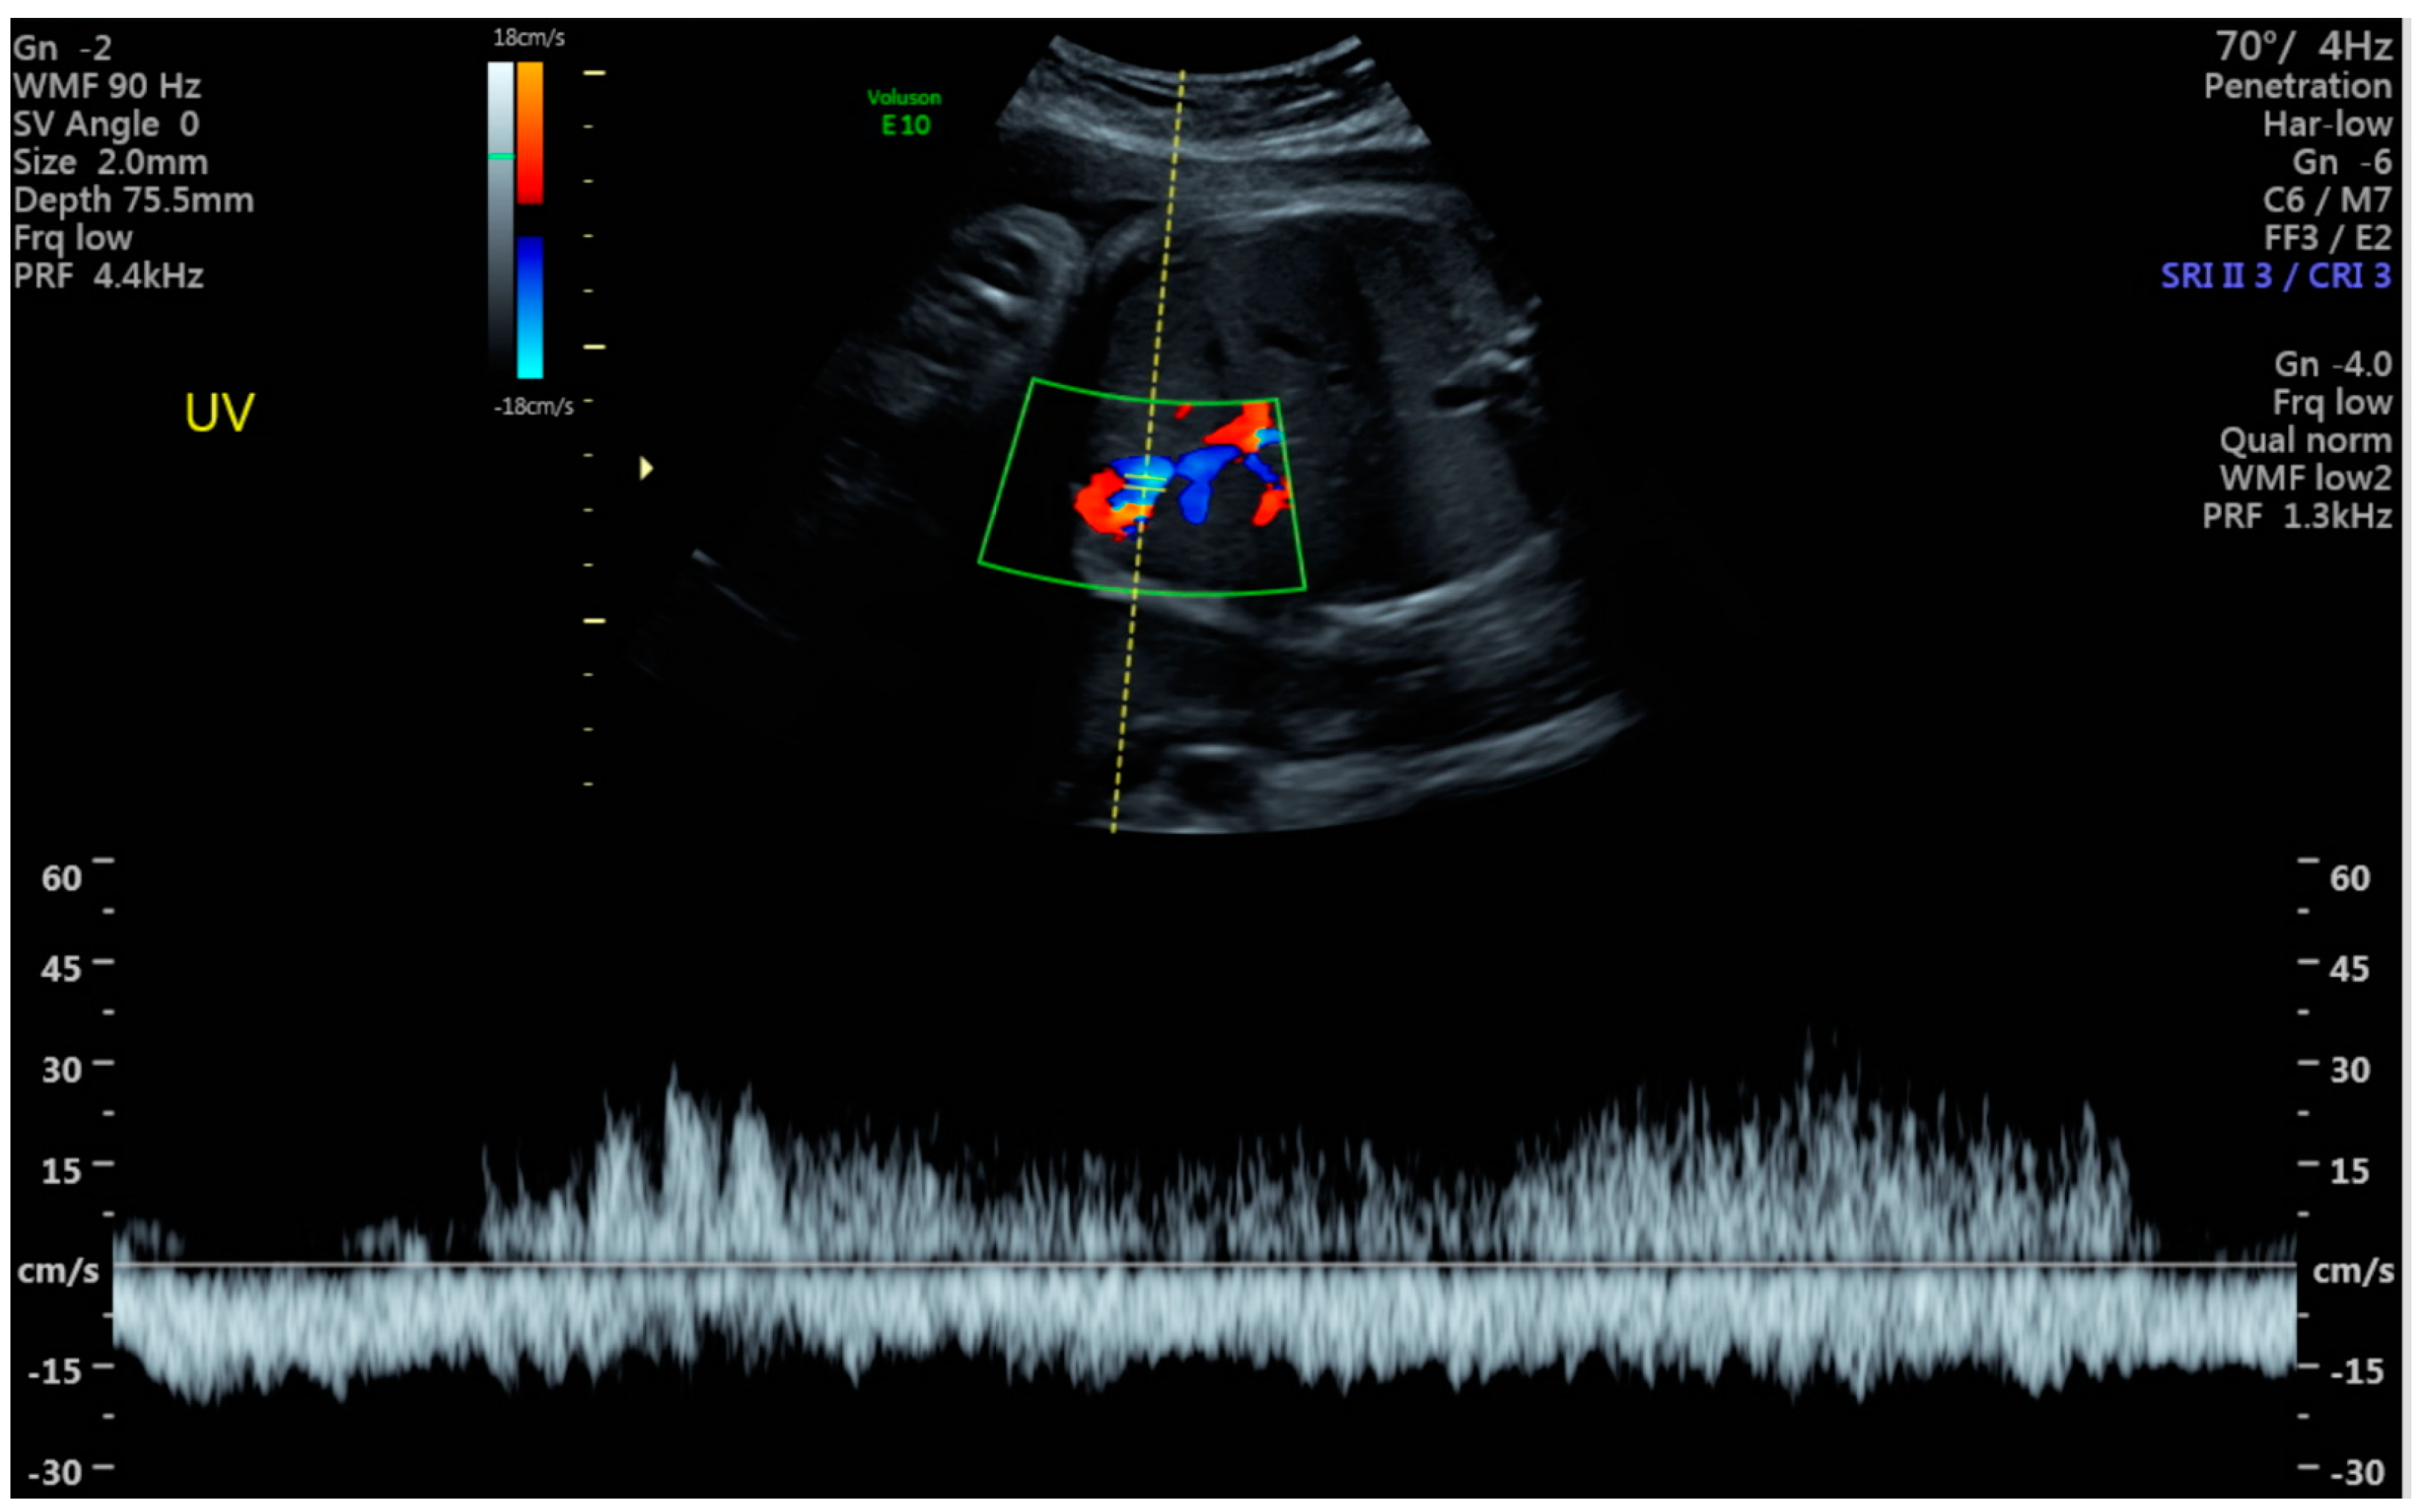

3. Diagnosis

6.4. Turbulent Flow in UVV